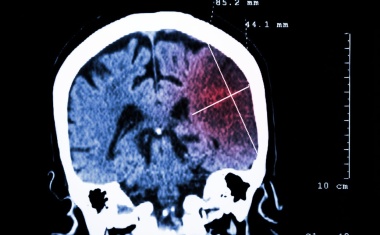

Die Spezialstation für Schlaganfallpatienten der Zentralklinik Bad Berka, die Stroke Unit, ist erneut zertifiziert worden. Die vier Betten-Station für die Akutbehandlung, Diagnostik und frühestmögliche Rehabilitation von Schlaganfallpatienten erhielt die Auszeichnung durch die Zertifizierungsgesellschaft InterCert.